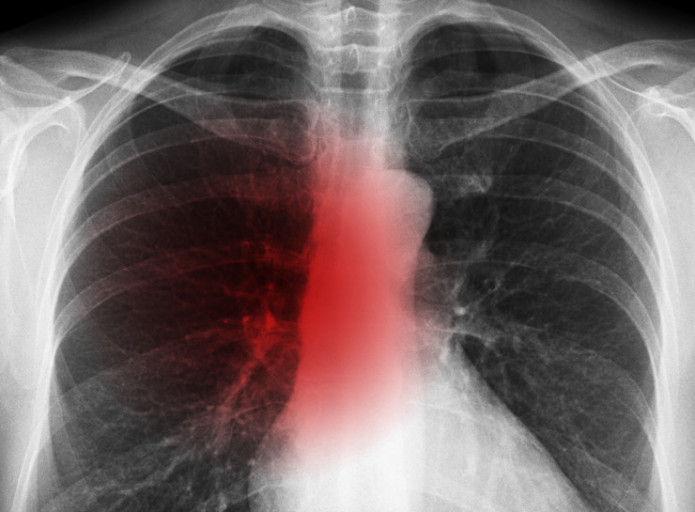

폐암은 위암, 갑상선암 다음으로 3번째로 발병 빈도가 높은 3대 암 중 한 가지입니다. 폐암은 재발과 전이까지의 빈도도 잦은지라 완치가 어렵다고 하며 폐암 발병 초기에는 거의 증상이 없을 수가 있어 수술이 불가능한 3기, 혹은 4기에 주로 진단된다고 합니다.

폐암 4기에 이르게 되면 5년 생존률이 30% 대로 떨어지게 된다고 합니다. 그리해서 폐암은 암 질병이자 중 사망자 비율이 가장 높은 것으로 나타나고 있습니다.

폐암은 사망률 2위를 차지하고 있는 간암에 비해 무려 2배에 가까운 사망률을 보이고 있다고 해요. 이렇게 치명적인 폐암에 대해 미리 알고 대처하는 것이 바람직할 것 같습니다. 아래에서는 폐암이라 판단해 볼 수 있는 그 초기증상에 대해 간단히 설명드리겠습니다.